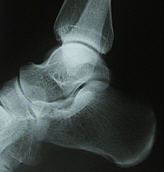

Stefans bessere Hälfte, die Unfallchirurgin ist, hat sich das Röntgenbild angeschaut. Ihre 90%ige Diagnose "Kantenabsprengung (kleiner Bruch)".

Mmmh ... das auch noch, würde 4-6 Wochen Gips bedeuten :(.

Doch wie bringe ich diese zweite Diagnose dem Arzt in Landstuhl bei ? Soll ich sagen "ich hab das Röntgenbild mit meiner Digi fotografiert, als sie noch nicht im Zimmer waren, und dann habe ich es im Tagebuch veröffentlicht, es hat sich ein netter Leser gemeldet, dessen Frau Unfallchirurgin ist und die hat gemeint, es sei eine Kantenabsprengung, bitte schauen sie nochmal nach" ... ich weiß doch, wie Ärzte auf eine zweite Meinung reagieren.

Mit diesem Fuß:

Arzt drückt drauf, Beate schreit Aua. Arzt meint "röntgen". Gesagt, getan.

Während ich rein gar nix erkenne, ordnet Arzt weitere Maßnahmen an:

Und so sitzt Beate nun zu Hause, ist krankgeschrieben, hat eine Gipsschiene, einen Außenbandriß und ist (zumindest bis jetzt noch) die unbequemste Patientin, die man sich vorstellen kann. Will sich nicht helfen lassen, nicht abhängig sein, weiter alles alleine machen ... dabei wäre sie mit ihren Krücken in der Küche grad nochmal hingefallen, weil der Läufer weggerutscht ist. Gottseidank stand ich hinter ihr, so dass sie wohlbehütet in meine Arme fiel.